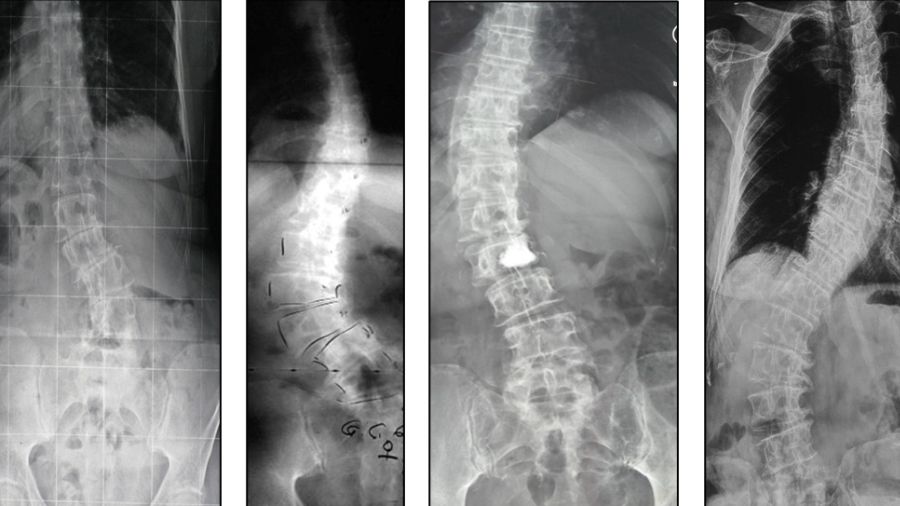

However, some patients have multiple congenital deformities, including as many as seven to ten segments. In very long curvatures like those we will consider more growth-friendly techniques, such as a growing rod. The growing rod is effective in protecting lung volume and thoracic cage volume, but it does need to be lengthened every six to nine months.

The most common postoperative risks are late infection or implant problems. If we acquired insufficient fusion in surgery, we could see implant pull-outs or with rod or screw breaks. A rod break is a fairly typical complication because you have upper and lower fixation with nothing in between, so it’s biomechanically weak.

One promising innovation in the field is the development of magnetically-controlled growing rods, which can be adjusted using a small machine externally to lengthen the rod as the patient grows. This has potential to prevent the need for so many repeat surgeries, but the company who produces them has had issues with debris coming out into the body over time, so they don’t recommend keeping them in the body for more than two years. As a result, I have reverted to conventional growing rods, but I hope to see more development in this field in the future.